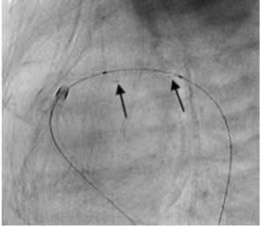

成功应用IBS Angel™对动脉导管进行开通。术后即刻随访结果显示支架形态结构良好,患者动脉导管内血流通畅。